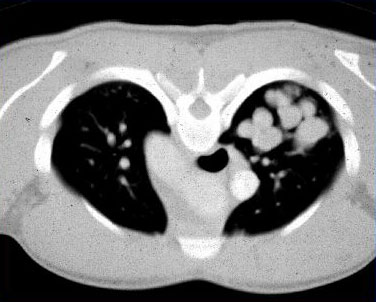

Aspergilose broncopulmonar alérgica

Tomografia computadorizada (TC) do tórax em um paciente com aspergilose broncopulmonar alérgica (ABPA): vias aéreas bronquiectásicas dilatadas impactadas por muco

Do American College of Chest Physicians, PCCU Volume 17, Lesson 17: Allergic bronchopulmonary aspergillosis; usado com permissão